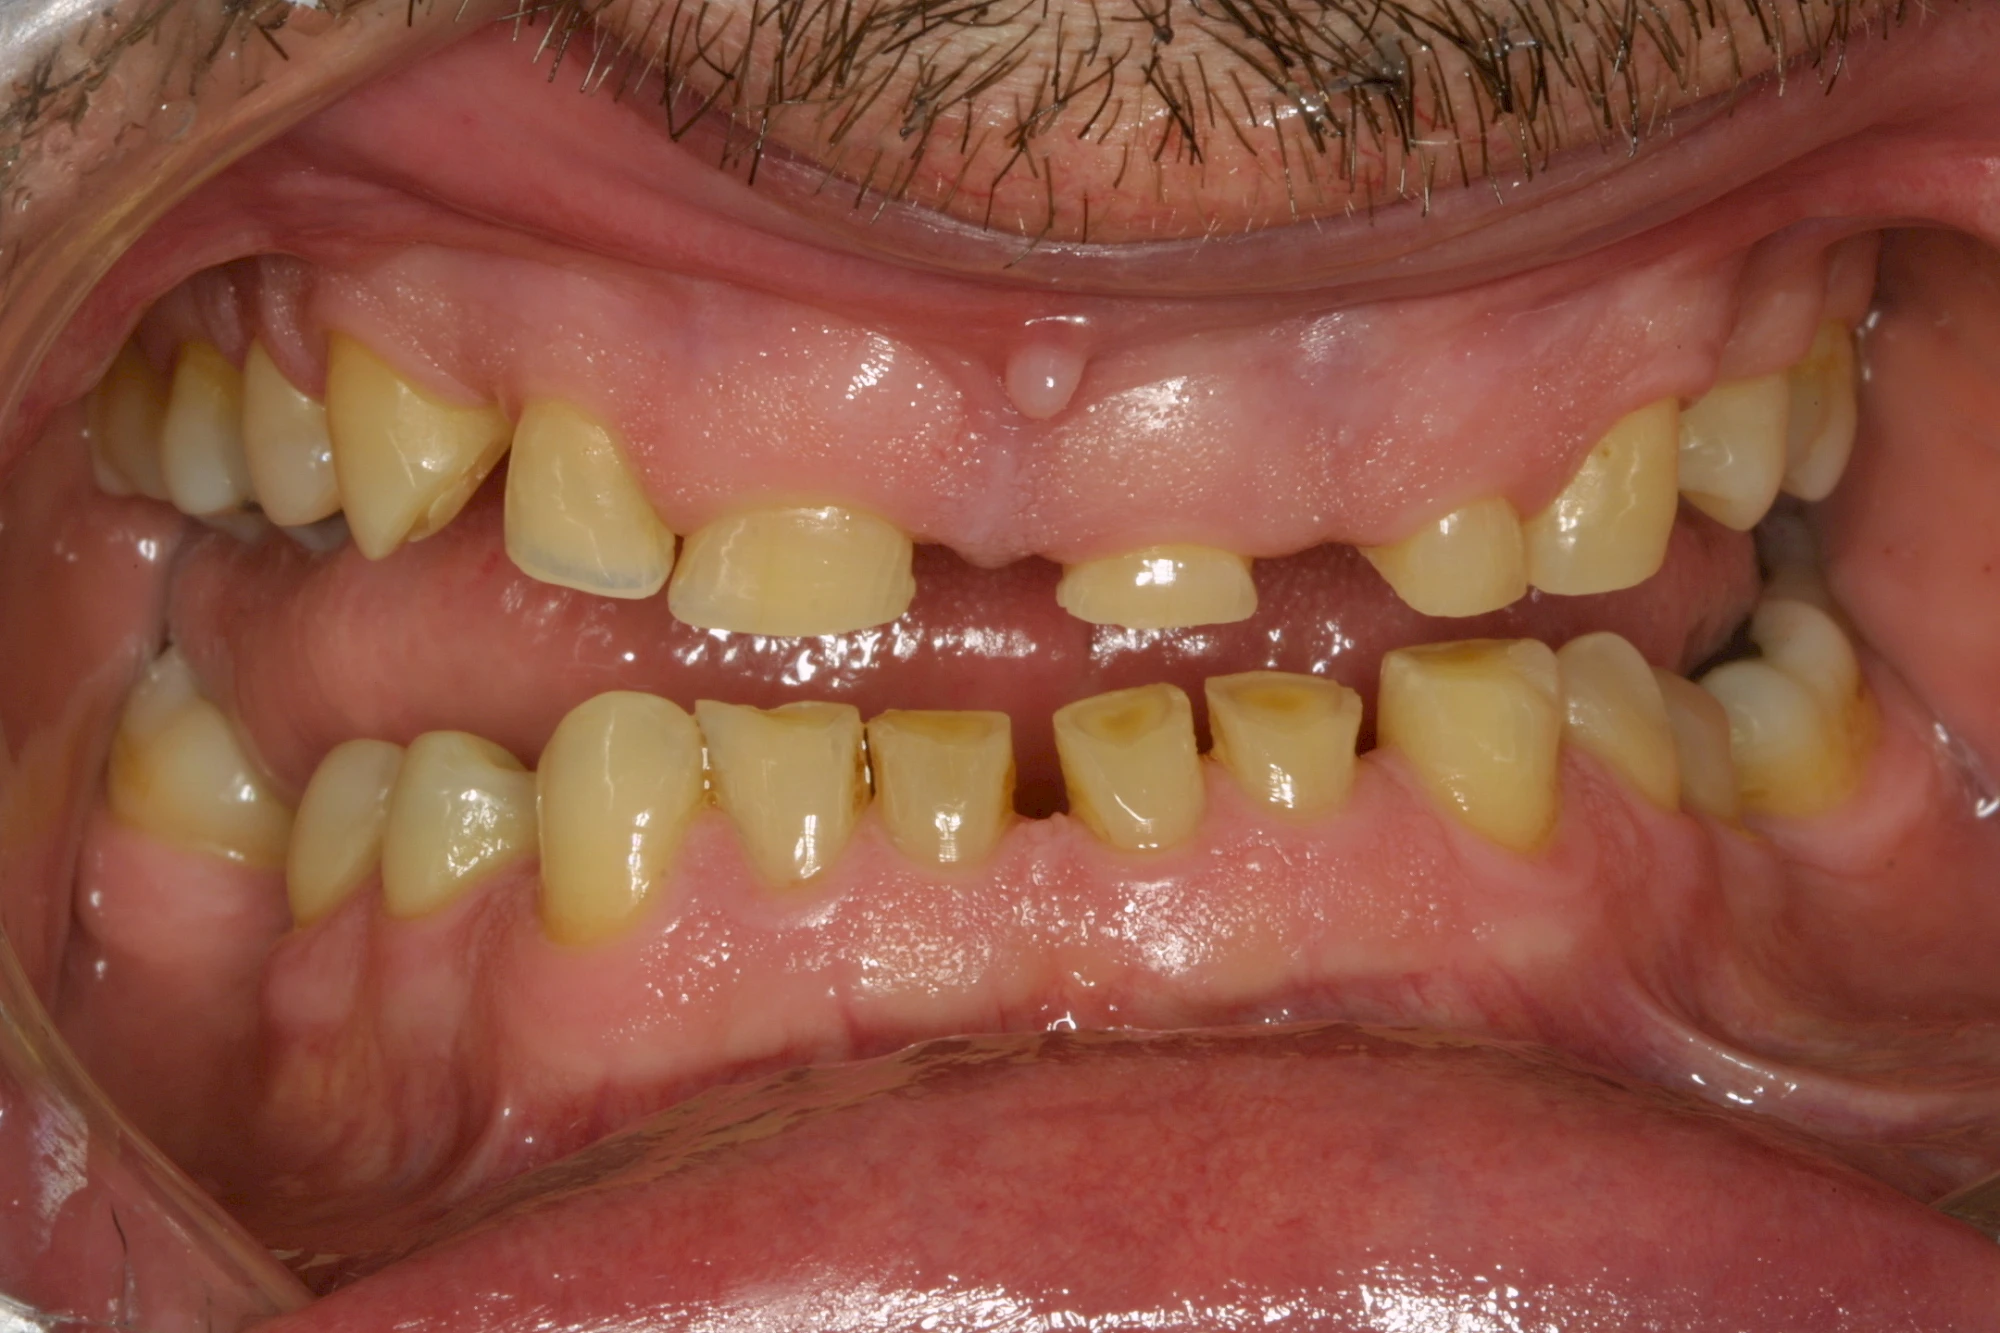

Keilförmiger Defekt

Eine Sonderform sind sogenannte keilförmige Defekte im Bereich der Zahnhälse. Hier geht man davon aus, dass Knirschen und Pressen in Kombination mit falschen Putzgewohnheiten (zu hoher Putzdruck, Verwendung von Zahnpasta mit hohen Abrasionswerten) eine Rolle spielen.